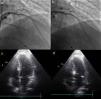

O procedimentoA intervenção inicia-se por uma coronariografia, com identificação da artéria alvo, habitualmente a primeira septal que se ramifica na porção basal do septo, sendo visível nesses vasos a presença de milking sistólico (Figura 1a). Por vezes a septal alvo pode originar-se de uma diagonal, da circunflexa ou mesmo da coronária direita, o que não aconteceu na nossa população. A avaliação da anatomia coronária, da facilidade de acesso ao vaso alvo e do seu calibre, permite a escolha do material a utilizar. Foram usados habitualmente cateteres guia Judkins e EBU de 6F, fios guia BMW® ou Pilot 50® (Abbott Vascular, Santa Clara, Califórnia, EUA) e cateteres de balão over the wire Apex Flex® (Boston Scientific, Natick, MA, EUA). Privilegiou-se a via femoral para favorecer uma maior estabilidade durante a cateterização coronária. Na presença de lesões coronárias significativas e com indicação para revascularização, consideramos que esta deverá ser efetuada primeiro e a ASA protelada para um segundo tempo, após reavaliação das queixas. Num doente da nossa população a origem da septal alvo relacionava-se com uma lesão da descendente anterior, ficando o seu posterior acesso provavelmente comprometido pela colocação do stent, pelo que se optou por realizar primeiro a ASA e de seguida tratar a lesão no mesmo tempo.

Procedimento. a) Angiografia com incidência oblíqua-direita-cranial da coronária esquerda, mostrando septal alvo. b) Cateterização seletiva da septal alvo com colocação de cateter de balão. c) Angiografia seletiva da septal alvo, com injeção de contraste através do lúmen do cateter de balão. d) Ecocardiografia transtorácica em quatro câmaras. Septo basal hipercogénico após injeção de contrate intramiocárdico, através do lúmen do cateter de balão.

Durante o procedimento é efetuada uma primeira avaliação por ecocardiografia transtorácica em que se pretende sobretudo avaliar a ecogenicidade das estruturas cardíacas, para comparação posterior e excluir a existência de derrame pericárdico. Com a confirmação da existência de um vaso alvo é colocado no ventrículo direito um electrocateter para pacing provisório, por via transvenosa femoral ou jugular e após a confirmação da sua posição estável e eficaz é administrada a heparina (70-100U/kg). De seguida, a septal alvo é abordada com um fio guia previamente introduzido no cateter de balão. Através do fio guia o cateter de balão é introduzido no vaso alvo e colocado na zona pretendida (Figura 1b). Esta é escolhida de acordo com o diâmetro do vaso e a existência de bifurcações, a incluir ou não na injeção de álcool, dependendo da sua importância e trajeto. O diâmetro do balão deve ser 0,5mm superior ao calibre do vaso alvo na zona onde se efetuará a insuflação. Um calibre menor pode não ocluir completamente o vaso e permitir o refluxo de álcool para a descendente anterior, por outro lado o sobredimensionamento pode levar ao deslocamento do balão durante a injeção.

Após a insuflação do balão a baixa pressão (4-6ATM) o fio guia é retirado do seu lúmen e através deste é realizada uma injeção com contraste angiográfico, a qual permite visualizar a circulação distal do vaso alvo, excluir a presença de colaterais e confirmar a total oclusão com a ausência de refluxo de contraste para a descendente anterior (Figura 1c). De seguida são injectados 1-2cc de contraste intramiocárdico, inicialmente foi utilizado Levovist® (Bayer AG, Schering AG, Alemanha) e após a sua descontinuação alterou-se para SonoVue® (Bracco, Milão, Itália). Por ecocardiografia transtorácica confirma-se a hiperecogenecidade da região alvo, o septo basal onde ocorre o SAM e a turbulência do fluxo, e exclui-se o envolvimento de regiões remotas, como a parede livre do ventrículo esquerdo, o ventrículo direito e os músculos papilares (Figura 1d).